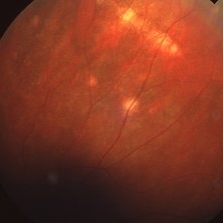

Linear Histo Streak

Linear Histo Streak

Mar 27 2019 by Gary R. Cook, MD, FACS

53-year-old female with presumed ocular histoplasmosis demonstrating a depigmented linear histoplasmosis streak in the temporal periphery; V.A. = 20/20.

Imaging device: Topcon VT-50

Condition/keywords: presumed ocular histoplasmosis syndrome (POHS)